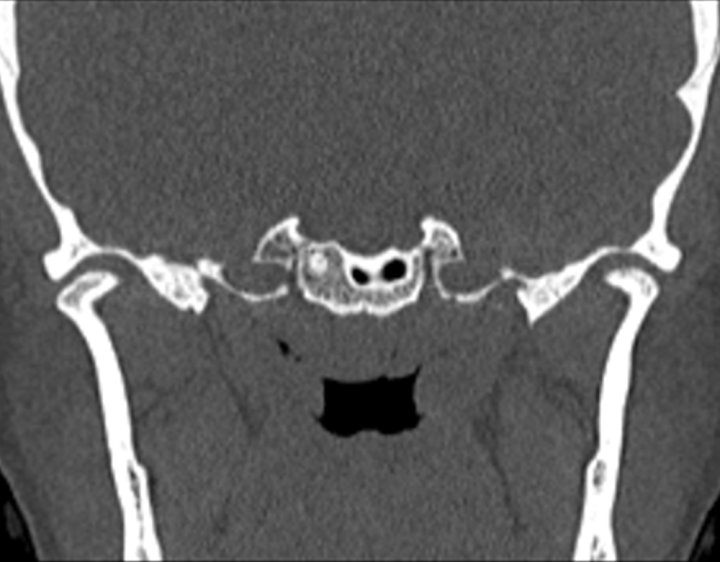

Click any image for labels.